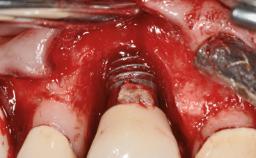

Oral implants are highly successful and offer long-term benefits, especially in the rehabilitation of edentulous patients or patients with oral defects following ablative tumor surgery (Albrektsson and coworkers 1986), and also after radiation therapy (Schiegnitz and coworkers 2014). With the number of implants placed globally going into the millions, implant dentists have observed some rare adverse events. Although carcinogenesis around implants is an exceedingly rare phenomenon, we recently reported about 15 patients treated for carcinomas adjacent to implants at our clinical department over a period of fifteen years (Moergel and coworkers 2014). The following case represents a patient of this cohort; it discusses possible risk factors and makes suggestions for a recall schedule. A 70-year-old woman was referred to our outpatient department for evaluation of a rapidly growing macroscopic alteration of the mucosa in the left mandible.